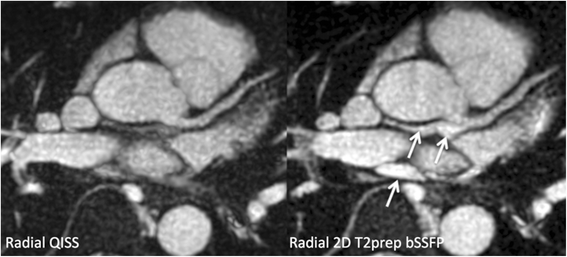

Methods: The left coronary circulation was imaged in six healthy subjects and two patients with coronary artery disease. Breath-hold QISS was compared with T2-prepared 2D balanced steady-state free-precession (bSSFP) and free-breathing, navigator-gated 3D bSSFP.

Results: Approximately 10 2.1-mm thick slices were acquired in a single ~20-s breath-hold using two-shot QISS. QISS contrast-to-noise ratio (CNR) was 1.5-fold higher at 3 Tesla than at 1.5 Tesla. Cartesian QISS provided the best coronary-to-myocardium CNR, whereas radial QISS provided the sharpest coronary images. QISS image quality exceeded that of free-breathing 3D coronary MRA with few artifacts at either field strength. Compared with T2-prepared 2D bSSFP, multi-slice capability was not restricted by the specific absorption rate at 3 Tesla and pericardial fluid signal was better suppressed. In addition to depicting the coronary arteries, QISS could image intra-cardiac structures, pericardium, and the aortic root in arbitrary slice orientations.

Conclusions: Breath-hold QISS is a simple, versatile, and time-efficient method for coronary MRA that provides excellent image quality at both 1.5 and 3 Tesla. Image quality exceeded that of free-breathing, navigator-gated 3D MRA in a much shorter scan time. QISS also allowed rapid multi-slice bright-blood, diastolic phase imaging of the heart, which may have complementary value to multi-phase cine imaging. We conclude that, with further clinical validation, QISS might provide an efficient alternative to commonly used free-breathing coronary MRA techniques.